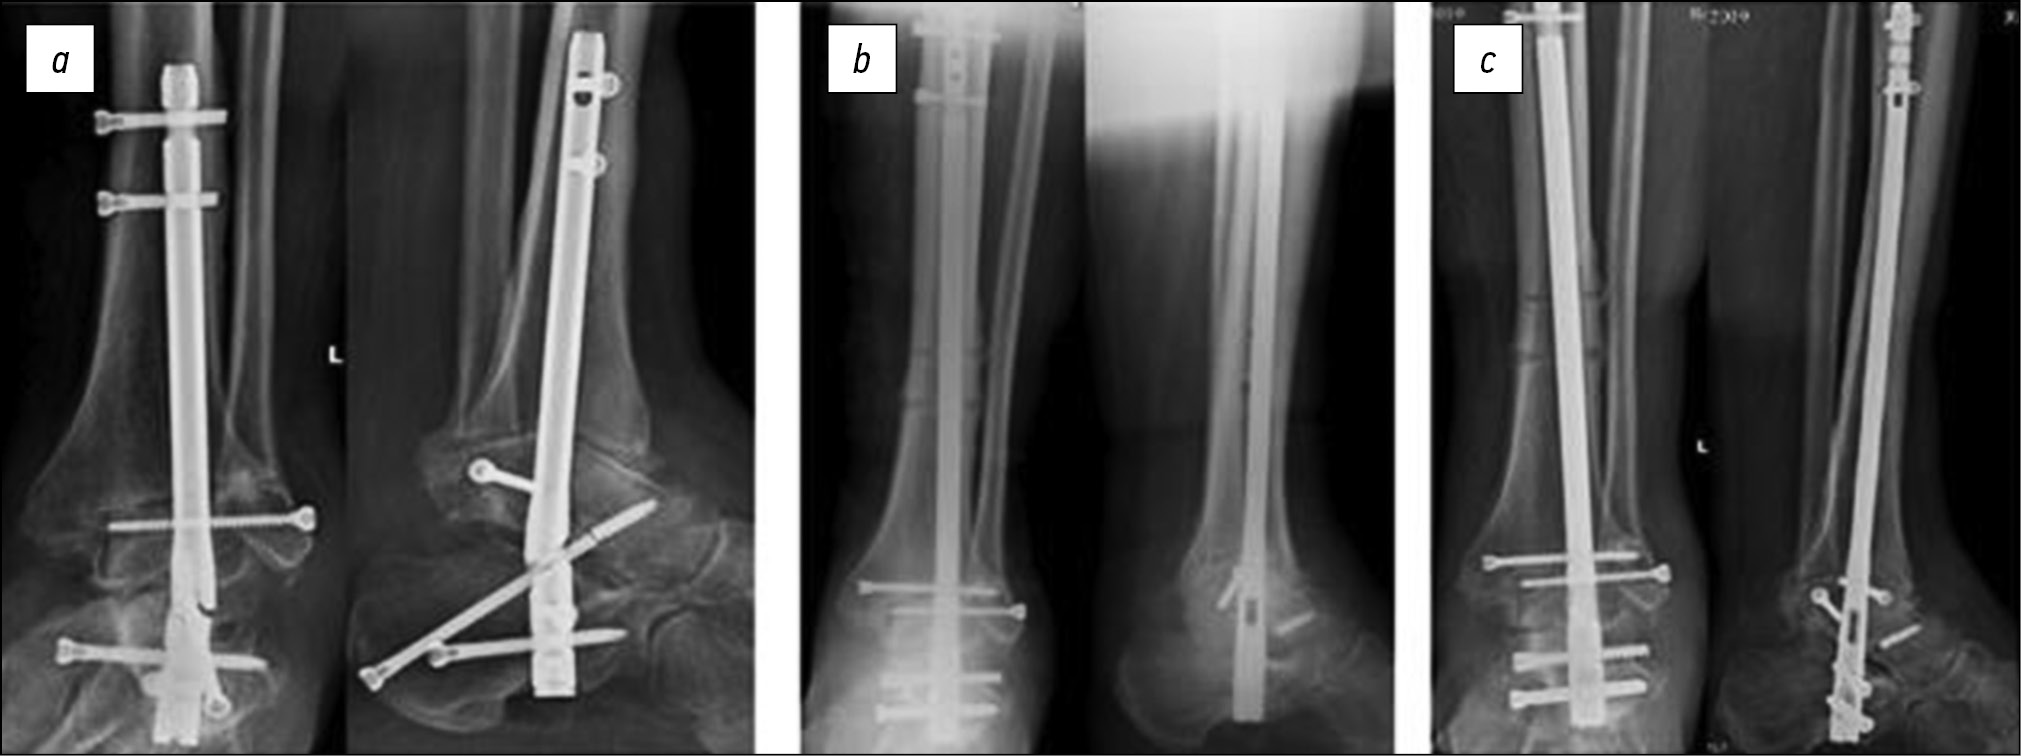

Больная П., 52 года, госпитализирована повторно через 3 месяца после выполнения первичной операции после падения в быту, до полученной травмы передвигалась с полной опорой на оперированную конечность без болевого синдрома. При обследовании выявлен перелом средней трети диафиза большеберцовой кости на уровне ранее установленных блокирующих винтов на фоне парциально сформированного костного анкилоза голеностопного сустава. В ходе ревизионного оперативного вмешательства выполнены удаление первично установленной металлоконструкции, реваскуляризирующая остеоперфорация таранной и большеберцовой кости по линии формирующегося анкилоза, закрытая репозиция перелома большеберцовой кости, ретроградный остеосинтез интрамедуллярным стержнем (рис. 4).

Рис. 4. Рентгенограммы больной П.: a — через 3 месяца после первичного оперативного вмешательства, b — после ревизионного оперативного вмешательства, c — через 12 месяцев после ревизионного оперативного вмешательства

Fig. 4. Radiographs of patient P.: a — 3 months after her first surgery, b — the revision surgery, and c — 12 months after the revision surgery